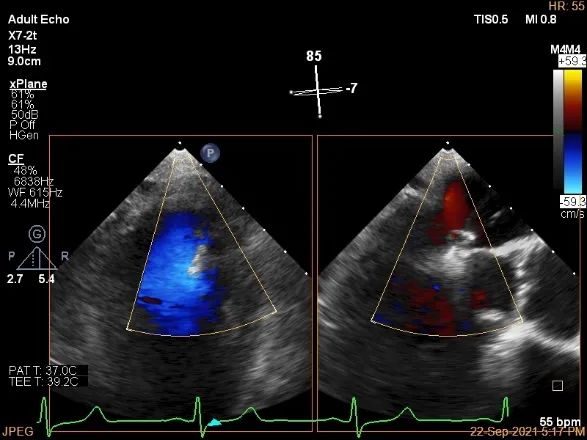

术中超声

3D:P1区脱垂并腱索断裂,Width:11.4mm

3D-color:重度MR,4级

麻醉状态下肺静脉血流频谱

MVA:7.8cm²,平均跨瓣压差:1mmHg

房间隔穿刺点选择

穿刺高度:4.08cm